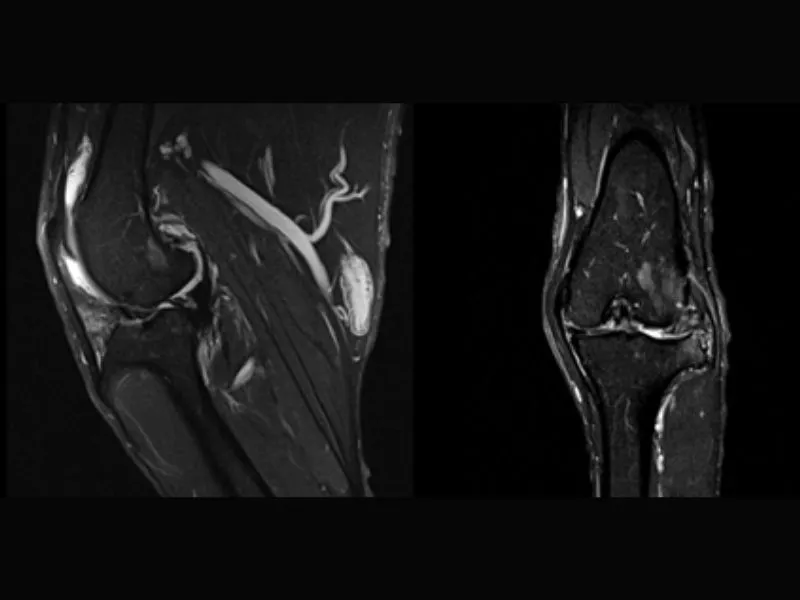

Clinical images

Small animals